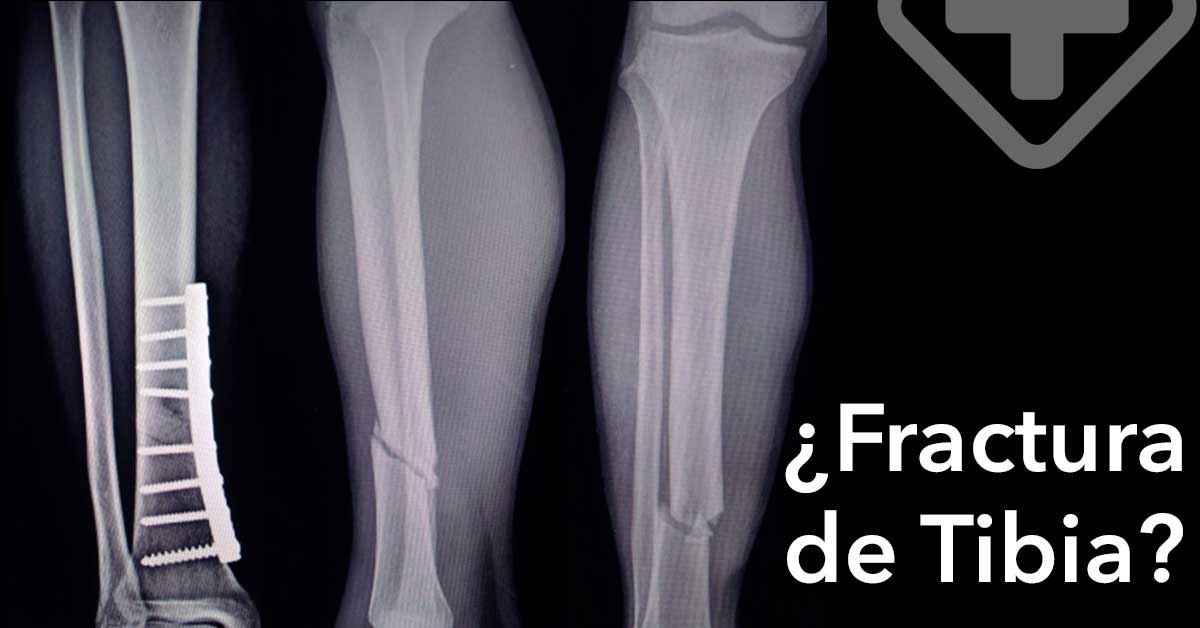

En casos severos, la cirugía puede ser necesaria para asegurar que el hueso sane correctamente. El Cirujano Ortopedista o Traumatólogo puede recurrir a placas y tornillos metálicos para fijar el hueso en su lugar, permitiendo la óptima recuperación del hueso con daño mínimo en el largo plazo. Este procedimiento es conocido como osteosíntesis.

El Cirujano Ortopedista o Traumatólogo puede también utilizar varillas o clavos metálicos para colocarlos a través de los huesos, por encima y debajo de la fractura. Estos se unirán a un marco rígido llamado fijador externo, y mantendrán el hueso en su lugar.